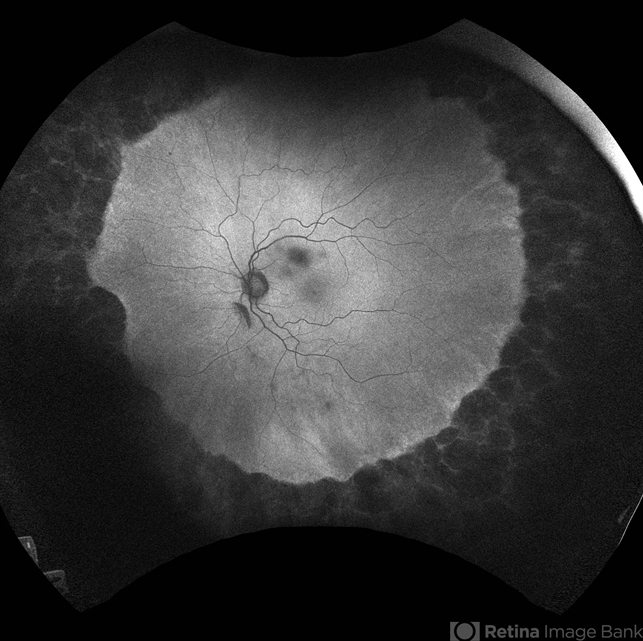

- Alagille Syndrome

- hereditary choroidal dystrophy, hereditary retinal degeneration

- 43 yo Female with known Alagille Syndrome, referred for peripheral retinal changes. Subjective nyctalopia but no other symtpoms. Alagille Syndrome UWF Autofluorescence.